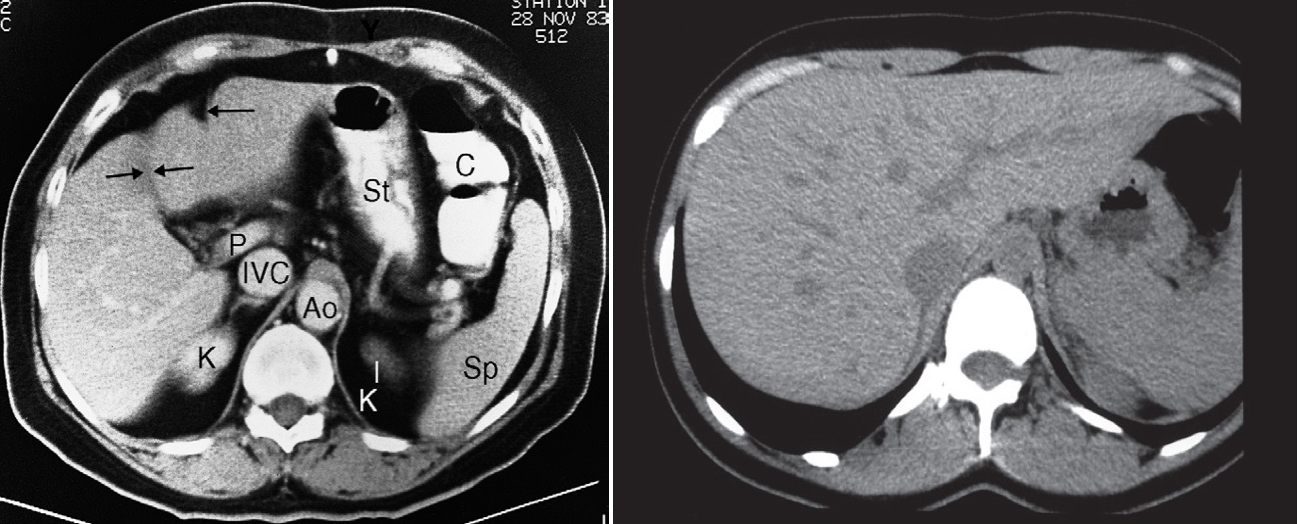

CT scan of normal liver (enhanced scan). Ao, aorta; C, colon; IVC, inferior vena cava; K,kidney; P, portal vein; Sp, spleen; St, stomach. The single arrow indicates a fissure for the falciform ligament, and the double arrows a fissure for the gall bladder, which divides the liver into the right and left lobes.

in second image CT scan of normal liver showing unopacified veins, which should not be confused with metastases.